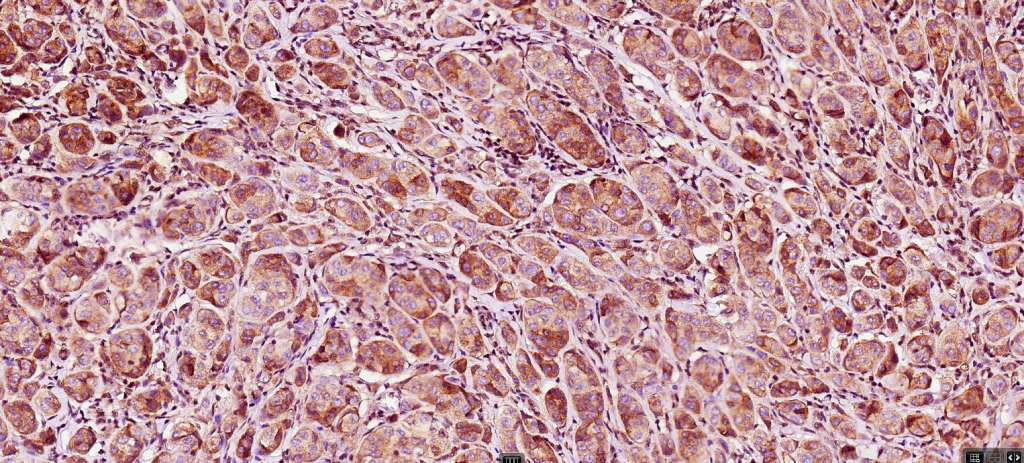

Combined common melanocytic nevus & BAP1-inactivated melanocytoma